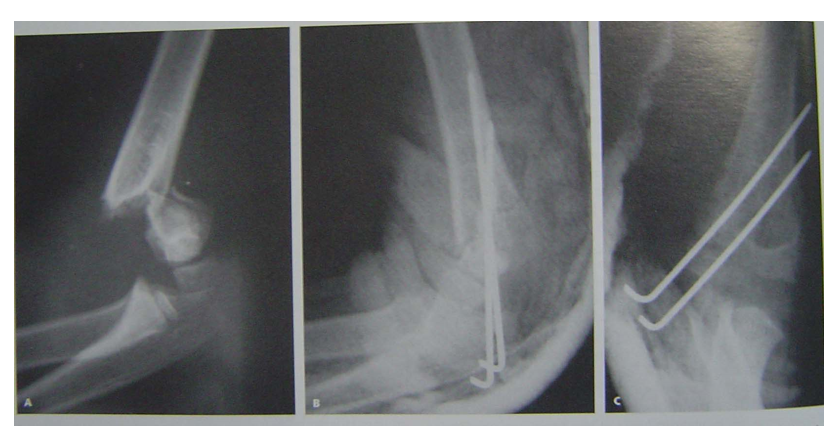

屈曲型伸直复位,伸直固定是方法之一。但石膏容易滑脱另一方法,伸直复位后屈曲肘关节,向后推挤维持复位,然后经皮克氏针固定。A、B术前x线片C 、D 手法复位 E 克氏针固定后